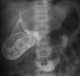

Biliary dilatation without jaundice or obstruction

May Be Caused by

Advanced age

Amebic liver abscess

Cholecystectomy

Choledochal cyst type I

Common duct exploration sequela

Early biliary ductal obstruction

Hydatid disease

Nonobstructive gallstone

Normal variant

Post-ductal obstruction

Recent passage of stone with ampullary edema